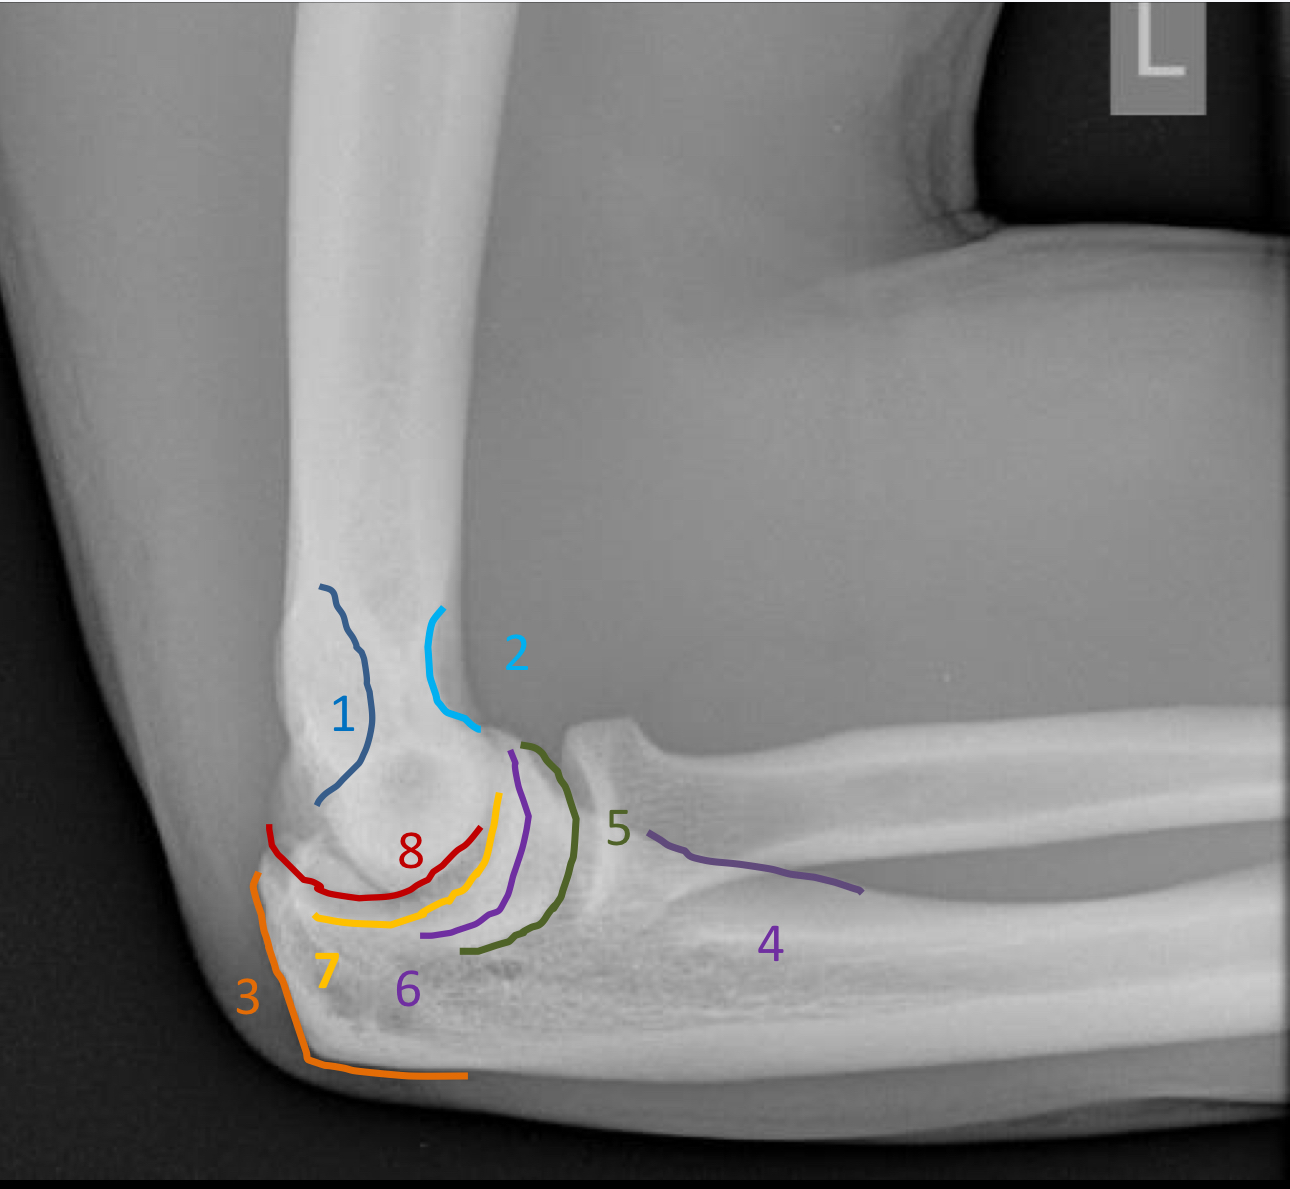

1?

olecranon fossa

2?

coronoid fossa

3?

olecranon process

4?

ulnar tuberosity

5?

capitellum

6?

trochlea

7?

trochlear notch

8?